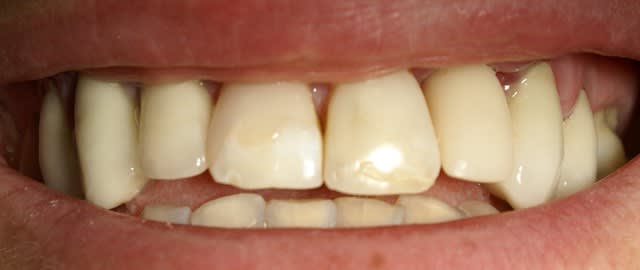

Jeune homme, 20 ans, accident de vélo.

Perte de 11 et 21.

Arrive dans mon cabinet 8 jours post trauma.

J'ai placer sous antibio et 2 jours après j'ai curetté les alvéoles, fait lambeau (perte de paroie buccale), placer 2 4,6 X 15 mm en palatin, greffe MINEROS, membranne (suturée sous le lambeau palatin + 2 tacs en titane au buccal).

Extension du lambeau au buccal et fermeture.

Ah oui, freinectomie laser en mêm temps, histoire de s'occuper un peu. Pas de temporisation sur implants avec une perte d'os au buccal. Prothèse acrylique amovible de transition, placée 7 jours post-op.

La 2e photo est 7 jours post-op, la sem dernière.

Zéro enflure, zéro douleur, pas d'anelgésique.